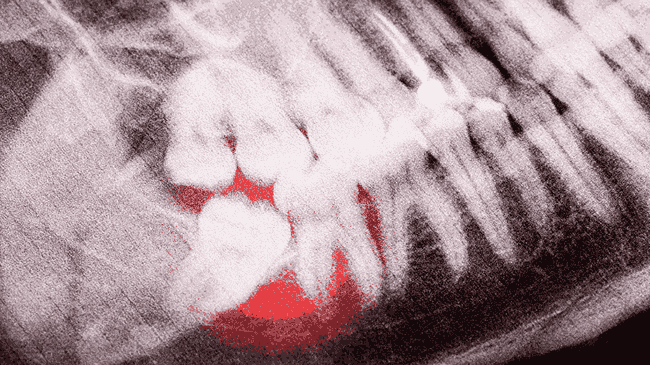

Ósemki są częstą przyczyną dolegliwości bólowych, nie tylko tych miejscowych, ale promieniujących do ucha, głowy, szyi. Dzięki regularnym wizytom u stomatologa i przeprowadzeniu precyzyjnej diagnostyki obrazowej (zdjęcia pantomograficzne lub tomografia komputerowa CBCT, możliwe jest wczesne wykrycie problemów i zaplanowanie odpowiedniego postępowania.